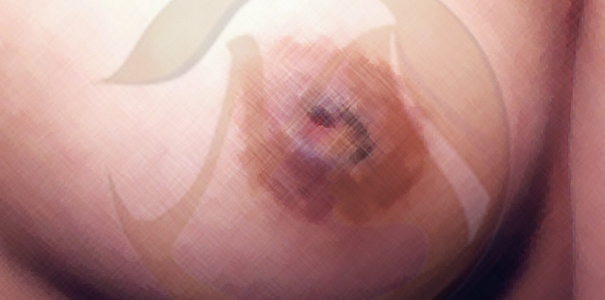

3단계

심하게 함몰되어 잘 당겨지지 않으며 꺼내면 바로 들어가버림